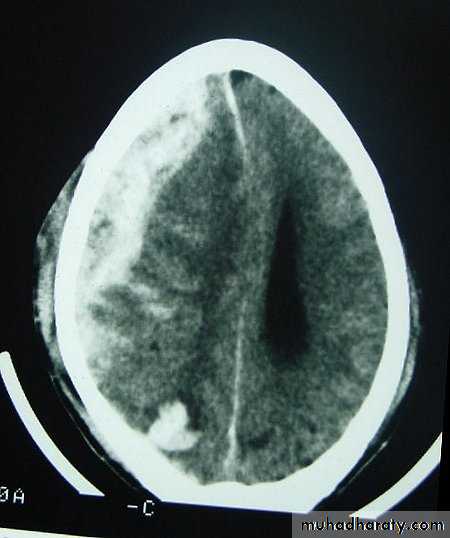

c. Intracerebral Haematoma

This is the least common of traumatic haematoma.They are due to areas of traumatic contusion coalescing into a contusional haematoma.

Disrupted cerebral tissue release thromboplastins that potentiate haemorrhage.

CT scan: appear as hyperdence lesions with associated mass effect and midline shift.Large intracerebral haematomas should be evacuated unless the patient’s neurological state is improving.

Small inracerebral haematomas may not require removal, but be aware that they can expand.